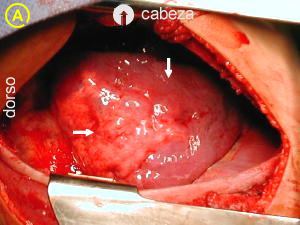

Foto B -

El muñón bronquial del lóbulo inferior derecho (Flecha blanca), suspendido en referencias listo para su cierre definitivo.

Flecha verde: el lóbulo superior derecho.

Flecha azul: el lóbulo medio.

Flecha negra: arterias lobares y vena pulmonar inferior ligadas.